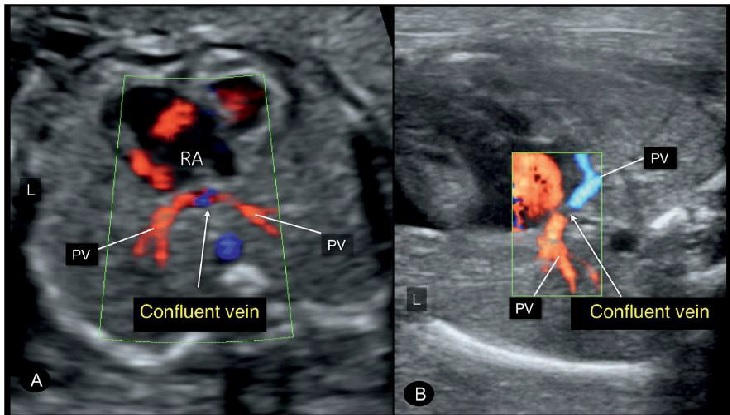

Hình 5: Hình ảnh mặt cắt ngang ngực 4 buồng tim, Doppler màu ở hai thai (A) và (B) đều có TAPVR, mỏm tim bên phải (dextrocardia) và kiểu hình bên phải (right isomerism). Lưu ý sự có mặt của các tĩnh mạch thu thập (confluent vein) phía sau tim. Doppler màu nên để ở thang vận tốc thích hợp và gain thấp để tách biệt rõ ràng giữa thành sau thất trái và tĩnh mạch thu thập (confluent vein).

Hình 8: (A) Hình ảnh Doppler màu mặt cắt ngang ngực thai thi có bất thường hồi lưu tĩnh mạch phổi toàn phần (TAPVR). Chú ý tĩnh mạch phổi phải (RPV) và tĩnh mạch phổi trái (LPV) không đổ vào nhĩ trái mà đổ vào tĩnh mạch thu thập (confluent vein), ngăn cách với nhĩ trái bởi một dải mỏng. (B) Tịnh tiến đầu dò về phía đầu thai nhi thấy hình ảnh mặt cắt ngang tĩnh mạnh đứng dọc (vertical vein) ở trong lồng ngực (mũi tên rỗng).